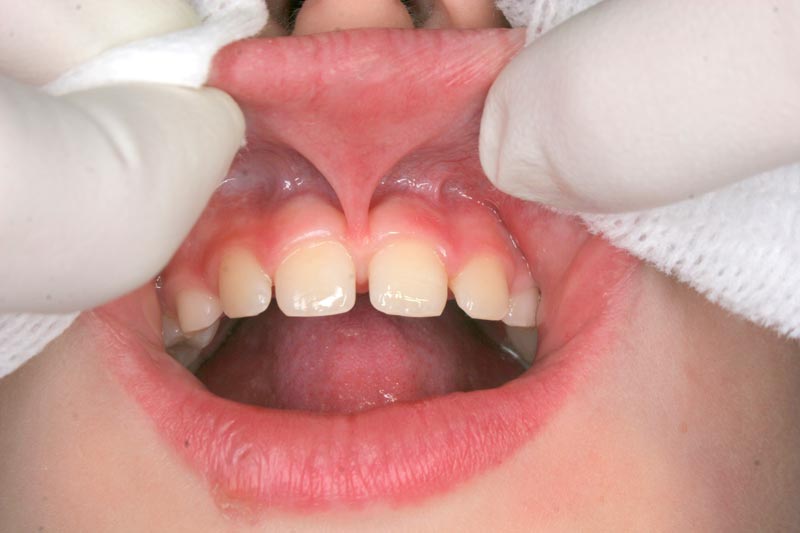

Frenulum (yüyən), diş əti toxuması (gingiva) ilə dil, dodaq və yanaq arasında yerləşən, toxumaları bir-birnə bağlayaraq hərəkətlərini sərhədləndirən yumuşaq selikli qişa toxumasıdır. Frenulum normal ölçülərdən böyük və qalın olduqda və ya diş əti kənarına yaxın yerləşdikdə bəzi narahatlıqlara və məhdudiyyətlətə səbəb ola bilir. Diş əti çəkilməsi, estetik məhdudiyyət, diastema, çıxan protez istifadə edən şəxslərdə protez fiksasiyasının məhdudlaşması və s. durumlar bununla bağlı ola bilir.

Sadalanan məhdudiyyətlərin ortadan qaldırılması və ya önünə keçilməsi məqsədilə frenulumun tamamən uzaqlaşdırılması (frenektomiya) həyata keçirilir. Bu prosedur həm ənənəvi cərrahi həm də lazer cərrahiyyəsi metodu ilə aparılır. Hansı metodun tətbiq edilməsi hər bir kliniki halda fərdi şəkildə qərara alınır.